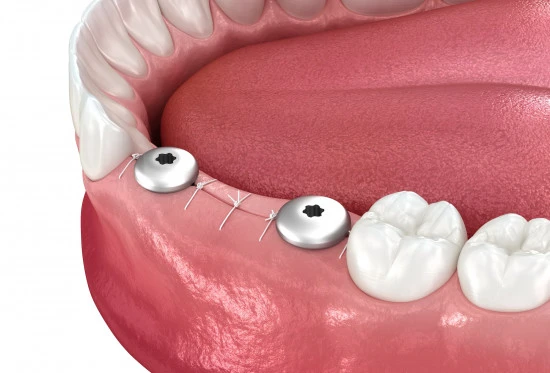

Формирователь десны используют в стоматологии, чтобы создать аккуратный десневой контур после имплантации.

Это такой небольшой винт с резьбой. Его вкручивают в верхнюю часть импланта. Размеры и форма зависят от клинического случая пациента, его анатомии и параметров искусственного корня.